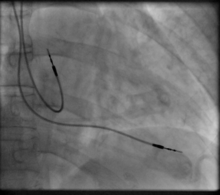

The first use of transvenous pacing in conjunction with an implanted pacemaker was by Parsonnet in the USA,[14][15][16] Lagergren in Sweden[17][18] and Jean-Jacques Welti in France[19] in 1962–63. The transvenous, or pervenous, procedure involved incision of a vein into which was inserted the catheter electrode lead under fluoroscopic guidance, until it was lodged within the trabeculae of the right ventricle. This method was to become the method of choice by the mid-1960s.

Transvenous pacing, when used for temporary pacing, is an alternative to transcutaneous pacing. A pacemaker wire is placed into a vein, under sterile conditions, and then passed into either the right atrium or right ventricle. The pacing wire is then connected to an external pacemaker outside the body. Transvenous pacing is often used as a bridge to permanent pacemaker placement. It can be kept in place until a permanent pacemaker is implanted or until there is no longer a need for a pacemaker and then it is removed.

Permanent pacing with an implantable pacemaker involves transvenous placement of one or more pacing electrodes within a chamber, or chambers, of the heart, while the pacemaker is implanted inside the skin under the clavicle. The procedure is performed by incision of a suitable vein into which the electrode lead is inserted and passed along the vein, through the valve of the heart, until positioned in the chamber. The procedure is facilitated by fluoroscopy which enables the physician to view the passage of the electrode lead. After satisfactory lodgement of the electrode is confirmed, the opposite end of the electrode lead is connected to the pacemaker generator.

A pacemaker is typically inserted into the patient through a simple surgery using either local anesthetic or a general anesthetic. The patient may be given a drug for relaxation before the surgery as well. An antibiotic is typically administered to prevent infection.[42] In most cases the pacemaker is inserted in the left shoulder area where an incision is made below the collar bone creating a small pocket where the pacemaker is actually housed in the patient's body. The lead or leads (the number of leads varies depending on the type of pacemaker) are fed into the heart through a large vein using a fluoroscope to monitor the progress of lead insertion. The Right Ventricular lead would be positioned away from the apex (tip) of the right ventricle and up on the interventricular septum, below the outflow tract, to prevent deterioration of the strength of the heart. The actual surgery may take about 30 to 90 minutes.